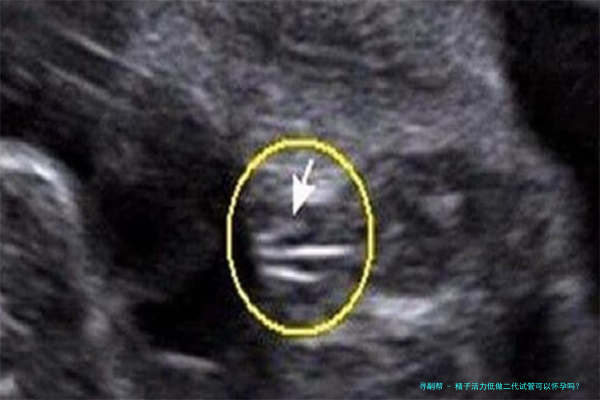

显微受精技术技术是在第一代试管婴儿技术基础上发展起来的一种更加邃密的操作方法。它通过显微操作技术,将单纯精子直接注入到卵子里面,进而达成受精过程。这一类方法绕开了精子自然穿透卵子的障碍,显著提高了受精率和胚胎发育的质量,尤其适宜于精子比较少、活力低或模样异常的患者。

四、ICSI操作:将筛选出的精子通过显微操作技术直接注入卵子里面。